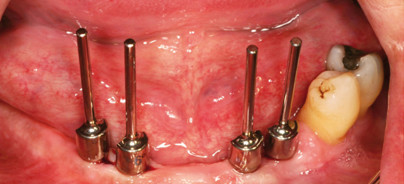

Das Standard-Behandlungsprotokoll der implantatprothetischen Versorgung zahnloser Kiefer beinhaltet im Oberkiefer vier bis sechs Implantate und im Unterkiefer vier ­Implantate mit SynCone Aufbauten. Bei sechs Implantaten je Kiefer haben sich die 5° Koni bewährt, während bei vier Implantaten die 4° Koni aufgrund der stärkeren Friktion zu bevorzugen sind. Die Aufbauten sind in unterschiedlichen Angulationen bis zu 30° erhältlich und ermöglichen durch die C/X-Plattform eine stufenlose Positionierung der gewinkelten Aufbauten um 360°. Dadurch wird eine einfache Ausrichtung auf eine gemeinsame Einschubrichtung und ideale Retention ermöglicht. Das SynCone-Abutment besteht aus zwei Koni: Der erste Konus dient als präfabrizierte Primärkrone zur Verankerung der Prothese. Der zweite, gegenüberliegende Konus wird in das Implantat inseriert und bildet eine hochfeste Verbindung zwischen Pfosten und Implantat. Mikrobewegungen und Abutmentlockerungen werden dadurch vermieden. Hart- und Weichgewebe bleiben langfristig stabil. Die präfabrizierte Konuskrone kann nur mit konischer Implantat-Abutment-Verbindungsgeometrie ohne Index funktionieren, da sich nur dann abgewinkelte Aufbauten durch Verdrehung auf eine gemeinsame Einschubrichtung ausrichten lassen (Torkelkonusprinzip). Die Konusverbindung des ANKYLOS-Systems ist selbsthemmend: die Zugschraube des Abutments fixiert den Aufbau zuverlässig im Verbindungs­konus des Implantats. Damit lassen sich mögliche Achs­divergenzen der Implantate einfach ausgleichen, was insbesondere für den Oberkiefer notwendig ist. Eine gemeinsame Einschubrichtung der präfabrizierten Primärkronen wird bequem durch Drehen und anschließendes Fixieren der abgewinkelten Abutments erzielt.

Ein 58-jähriger Patient wandte sich an uns mit dem Wunsch nach neuen Prothesen mit verbessertem Aus­sehen. Er beklagte, dass die bestehenden Interimsprothesen nicht halten, er die Zähne aufgrund einer ausgeprägten Bisssenkung nicht „zusammenbekommt“ und sich das Zahnfleisch um die verbliebenen Zähne 18, 34 und 35 wiederholt entzünde. Die weitere Anamnese und der anschließende Befund ergaben einen starken Nikotinkonsum (zwei Päckchen/Tag), parodontale Abszesse, Bruxis­­mus und starken Würgereiz. Darüber hinaus war der Biss um ca. 9mm abgesunken. Aufgrund der starken Oberkiefer-Atrophie und einer schmalen Basis bestand eine ausgeprägte horizontale Diskrepanz zwischen Ober- und Unterkiefer. Der Röntgenbefund zeigte retinierte und verlagerte Weisheitszähne 38, 48 und die stark ausgeprägten Masseteransätze aufgrund von Parafunktionen. Das Ziel unserer implantatprothetischen Rehabilitation schloss eine Bisshebung um ca. 9mm in zwei Schritten ein, die über Interimsprothesen für den Ober- und Unterkiefer erfolgen sollte. Als definitiven Zahnersatz wur-den implantatgestützte Teleskopprothesen geplant. Für den Oberkiefer wurden lediglich vier Implantate vor­gesehen, da der Patient keine Sinusbodenelevation wünschte. Aufgrund der Parafunktionen wurde auf einen großen Verbinder nicht verzichtet. Für den Unterkiefer wurde eine Cover Denture vorgesehen. Nach Zahnentfernung und einer parodontalen Behandlung als Infektionsschutz sowie einer Kieferrelationsbestimmung wurde eine Diagnostikschablone angefertigt. Es hat sich in der Praxis erfolgreich bewährt, dass es sich beim Einsatz ­einer Diagnostikschablone um einen entscheidenden Schritt bei der implantatprothetischen Planung handelt. Diagnostikschablonen nehmen das Ergebnis vorweg und geben dem Behandler damit Sicherheit von Beginn an. Sie eignen sich während der Therapie als Röntgen- und OP-Schablonen und lassen sich zur Abformung einsetzen. Im Verlauf der Therapie erfolgte im Oberkiefer eine Kieferkammspreizung beidseits sowie eine Augmentation mit Eigenknochen. Im Ober- und Unterkiefer wurden je vier Implantate mit Durchmesser 3,5mm inseriert. Der entscheidende Schritt für den langfristigen Erfolg von SynCone Restaurationen ist, den richtigen Zeitpunkt für die Verklebung der Kappen zu wählen. Es empfiehlt sich, diese erst nach Fertigstellung des Zahnersatzes zu verkleben. Die Sekundärteile sollten nicht ins nackte Prothesengerüst, sondern in den fertigen Zahnersatz geklebt werden. Damit umgeht man zwei Fehlerquellen: Zum einen wird eine spannungsfreie Verblockung durch die Suprakonstruktion gewährleistet. Zum anderen kommt es durch eine mögliche minimale Bisshebung beim Stopfen der Prothesenbasis nicht zu einem Friktionsverlust zwischen Patrize und Matrize.